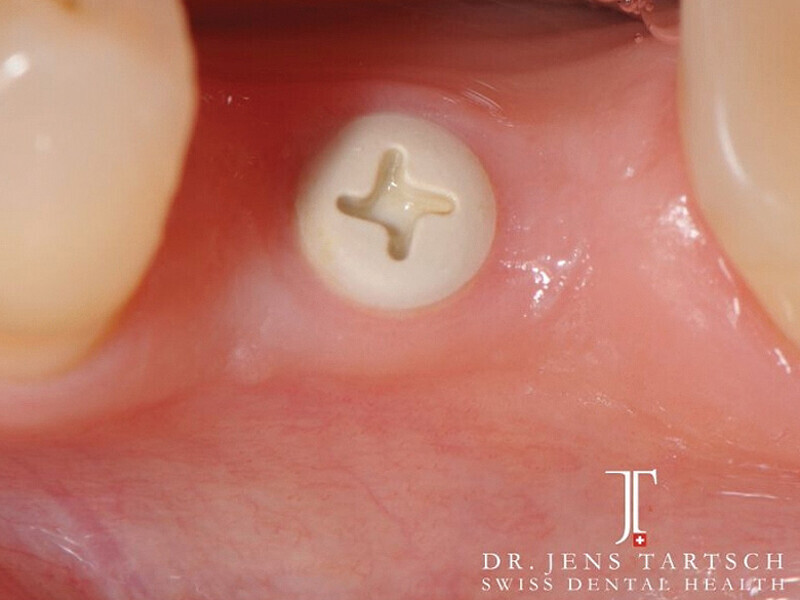

Fig. 12: Crown with composite closure of screw access channel. (Photo: Jens Tartsch, DMD)